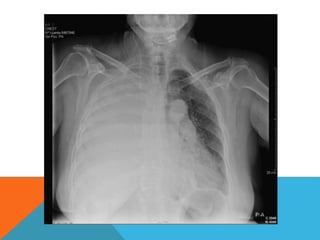

DERRAME PLEURAL

Es una acumulación patológica de liquido en la cavidad pleural

Se produce cuando se alteran las fuerzas homeostáticas que

controlan el flujo vascular y linfático que sale del espacio

DIAGNOSTICO DIFERENCIAL

Cuando hay presencia de un derrame existe

un desplazamiento contralateral del

DERRAME PLEURAL MASIVO

Puede darse por: